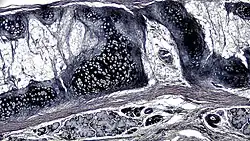

A cross section of mammalian elastic cartilage

Lateral side of the auricle

Elastic cartilage is histologically similar to hyaline cartilage but contains many yellow elastic fibers lying in a solid matrix. These fibers form bundles that appear dark under a microscope. The elastic fibers require special staining since when it is stained using haematoxylin and eosin (H&E) stain it appears the same as hyaline cartilage.[3] Verhoeff van Geison stains are used (giving the elastic fibers a black color), but aldehyde fuchsin stains, Weigert's elastic stains, and orcein stains also work.[3] These fibers give elastic cartilage great flexibility so that it is able to withstand repeated bending. Similarly to hyaline one or multiple chondrocytes lie between the spaces (or lacunea) in the fibres.[2] The chondrocytes only make up 2% of the tissue's volume.[2] Chondrocytes and the extracellular matrix are contained in an outerlayer named the perichondrium[2] (which is a layer of dense irregular connective tissue that surrounds cartilage which is independent of the joint).[3] It is found in the epiglottis (part of the larynx), and the pinnae (the external ear flaps of many mammals). Elastin fibers stain dark purple/black with Verhoeff's stain.